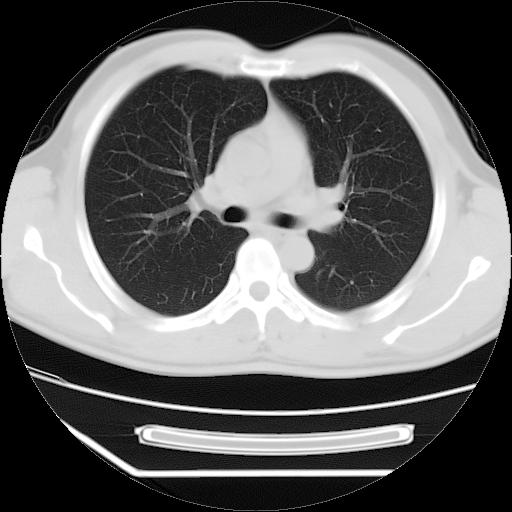

男,38岁,于2009年8月9日晚突发左侧胸痛,今x线提示左下肺阴影,为了明显确诊断,行ct检查,

血常规:嗜酸性细胞增高,单核细胞增高。

病灶发生在下叶,密度均匀,边缘模糊、毛糙,周围血管纹理增强扭曲改变,靠近胸膜处病灶胸膜反应明显。

支持考虑---球形肺炎。

左肺舌叶病变。主体病灶呈类圆形中心密度低,成液化趋势周边班片影分布

考虑肺脓肿

虽然实验室检查支持炎性病变,且病变内有坏死改变(中央呈大片状低密度影),但仍不能掉以轻心,鳞癌也可以有这种影像改变。